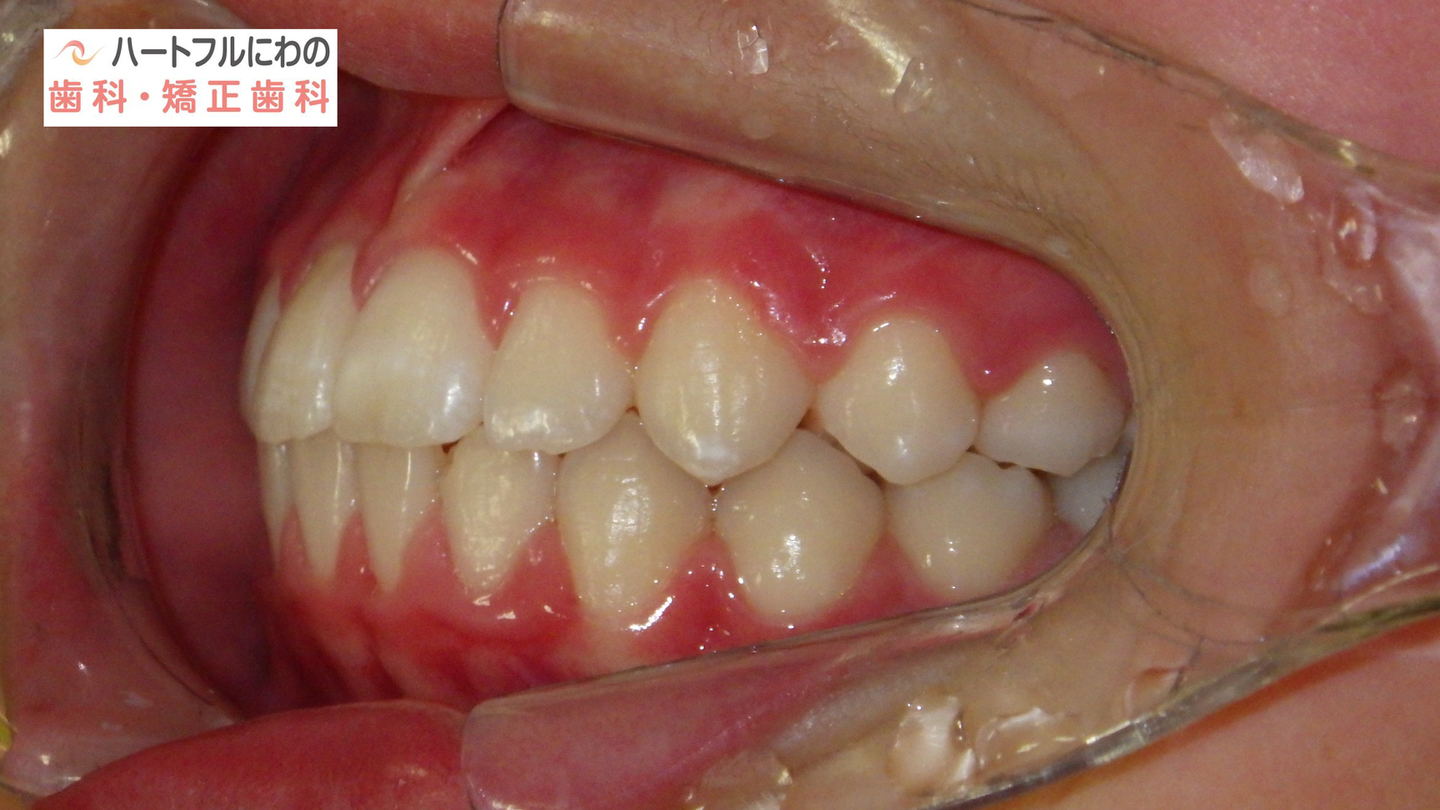

お口の中を拝見すると、上下の叢生(いわゆるガタガタ、乱ぐい)がみられ、多数の虫歯と歯肉炎がみられました。上唇小帯(上唇のすじ)の問題もありました。口呼吸で口腔内が乾燥すると通常の何倍も歯垢が付きやすくなり、虫歯や歯肉炎が頻発します。口呼吸の強い子は重なっている部分のかみ合わせが深い(下の歯がほとんどみえない)のもよく見られる特徴です。

奥歯と前歯の前後的位置関係は大きく改善し、正常になりました。